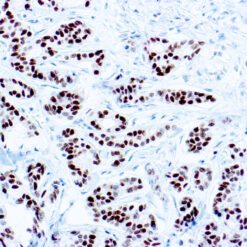

Cytokeratin (CAM5.2)

Anti-Cytokeratin (CAM 5.2) reagent has a primary reactivity with human keratin proteins that correspond to Moll’s peptides #7 and #8, Mr 48 and 52 kilodaltons (kd), respectively. Cytokeratin 7 and 8 are present on secretory epithelia of normal human tissue but not onstratified squamous epithelium. Anti-Cytokeratin (CAM 5.2) stains most epithelial-derived tissue, including liver, renal tubular epithelium, and hepatocellular and renal cell carcinomas. Anti-Cytokeratin (CAM 5.2) might not react with some squamous cell carcinomas.

| Positive Control Tissue | Colon, Lung, prostate and breast tissue. |